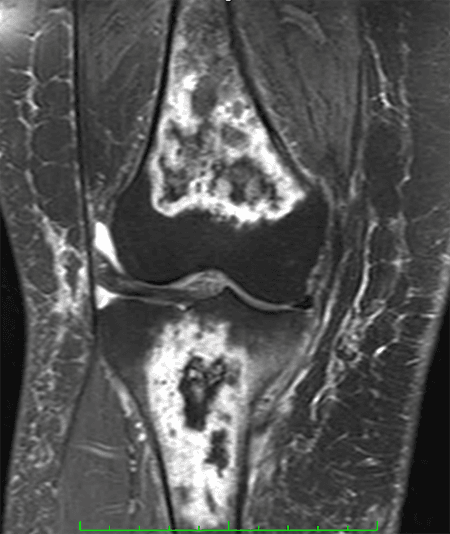

Paciente do sexo feminino, com 53 anos e quadro de dor crônica no joelho direito, principalmente na face anterior e medial. Ela refere piora da dor há uma semana, apresentando dificuldade na deambulação. Nega trauma e relata ter se submetido à cirurgia no tornozelo direito. Refere tratamento para asma brônquica com corticoide há anos.

Exames de imagem